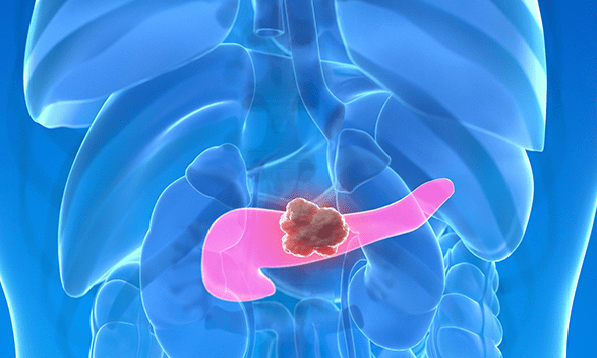

20~30대 췌장암 증가 이유는?

최근 발표된 국가암등록통계에 따르면 췌장암 환자는 과거 20년간 크게 증가했으며, 사망자도 지속적으로 늘어나고 있다. 1999년 이후 췌장암 환자는 약 3.7배 증가했으며, 같은 기간 사망자도 약 3배 가까이 증가했다. 췌장암은 전체 암 중에서는 상대적으로 발생 빈도가 낮지만, 사망률이 높은 암으로 꼽힌다. 최근 통계에서는 췌장암의 5년 상대 생존율이 약 16.5% 수준에 불과해 여전히 치료가 어려운 암으로 남아 … 더 읽기